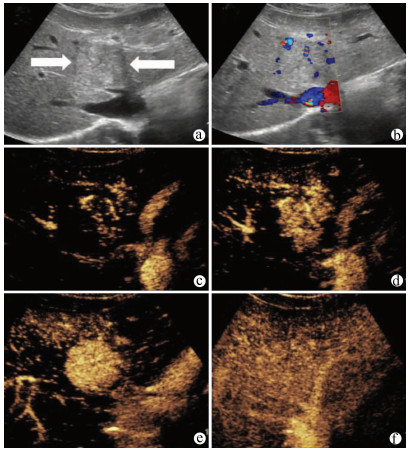

Guideline for ultrasonic diagnosis of liver diseases

Chinese Society of Ultrasound in Medicine, Oncology Intervention Committee of Chinese Research Hospital Society, National Health Commission Capacity Building and Continuing Education Expert Committee on Ultrasonic Diagnosis

2021, 37(8): 1770-1785. DOI: 10.3969/j.issn.1001-5256.2021.08.007

Abstract(3025) HTML (6526) PDF (9311KB)(794)

Abstract:

Ultrasound is a non-invasive, real-time, inexpensive, radiation-free and easily repeatable method, usually used for liver imaging. In recent years, new ultrasound examination techniques for liver diseases such as contrast-enhanced ultrasound and elastography have been rapidly developed, which can effectively identify intrahepatic space-occupying lesions, assess the degree of liver fibrosis and portal hypertension, and monitor the effects of treatment. Therefore, these technologies play an important diagnostic role in clinical liver diseases and have therapeutic interventional value. This guideline classifies the instrument set-up, patient preparation, and physician examination methods through multimodal ultrasound examinations (gray-scale ultrasound, color Doppler ultrasound, contrast-enhanced ultrasound, elastic ultrasound) for liver diseases. In addition, liver diseases multimodal ultrasound technology diagnostic criteria for diffuse hepatic lesions (inflammatory lesions, fibrosis, and sclerosis), multiple space-occupying lesions, and interventional procedures have been defined and standardized. Concurrently, we also recommend the ultrasound monitoring time interval and diagnostic report writing standard for liver diseases.